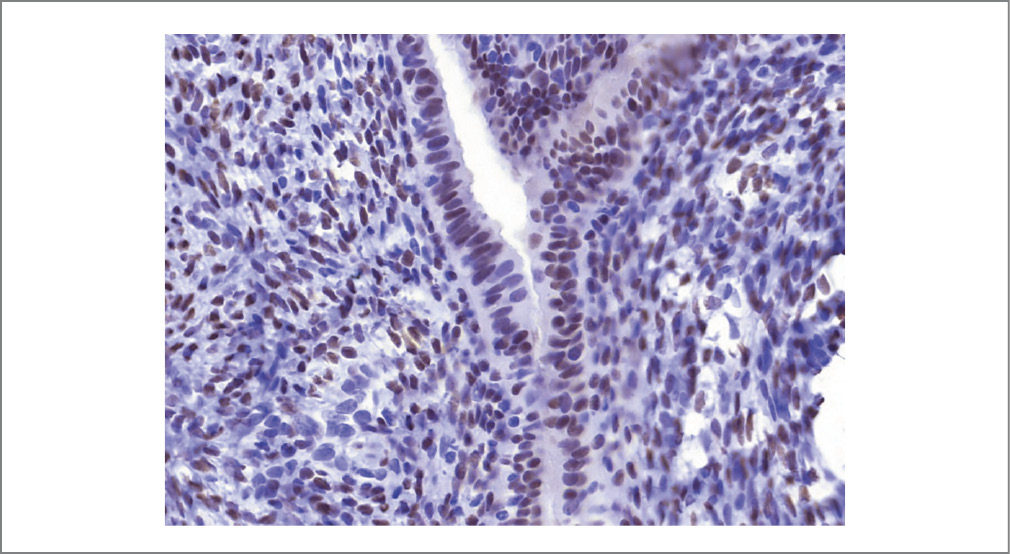

Рис. 7. Экспрессия PR в железах эндометрия. Иммуногистохимия. ×100.

Fig. 7. PR expression in the endometrial glands. Immunohistochemistry. ×100.

Рис. 8. Экспрессия PR в клетках эндометрия. Иммуногистохимия. ×350.

Fig. 8. PR expression in endometrial cells. Immunohistochemistry. ×350.

Результат патоморфологического исследования биопсийного материала (серо-розовая ткань плотно-эластичной консистенции, на разрезе белесоватого цвета, слоистого вида) представлен фрагментами новообразованной ткани, хаотично располагающимися мышечными волокнами с неравномерным разрастанием соединительной ткани, с фокусами соединительной ткани с участками, представленными эндометриоидными железами и стромой, по периферии – макрофаги, фагоцитирующие гемосидерин (рис. 3). При иммуногистохимическом исследовании выявлена умеренно выраженная экспрессия рецепторов эстрогена и прогестерона в клетках и железах эндометрия (рис. 4–8).